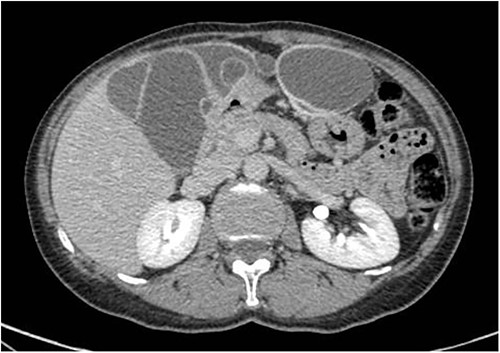

A 59-year-old woman presented to the abdominal surgery unit of our hospital for a dimensional increase of known epigastric multiloculated cystic formation detected on computed tomography (CT)-scan follow-up, with a maximum diameter of~20 cm (Fig. 1). Her medical history included breast and colon adenocarcinoma and scapular melanoma, all of which were surgically treated in addition to chemo, hormone and radiation therapies. The patient was asymptomatic. Blood tests were unremarkable. At explorative laparotomy, a voluminous multi-chambered and well-vascularized cystic formation was found (Fig. 2). Surgical excision was performed after ligation of the two vascular peduncles located in the small omentum (Fig. 3). Histological findings showed an angioleiomuscular tumor with cavernous aspects and uncertain potential for malignancy. The patient was discharged on postoperative day 4 without complications. At follow-up visits at 1, 3 and 6 months, the patient was in good condition with no disease recurrence.

Axial CT-scan highlighting the abdominal pluriconcameral cystic formation.